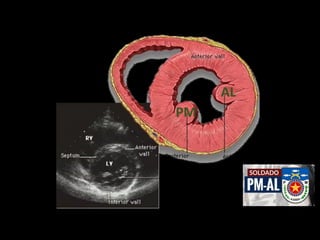

AL

PM

PARAESTERNAL EIXO CURTO

Paraesternal eixo curto mostrando os territórios irrigados pelas três principais artérias

coronárias: Descendente Anterior (DA), Circunflexa (Cx) e Coronária Direita (CD).